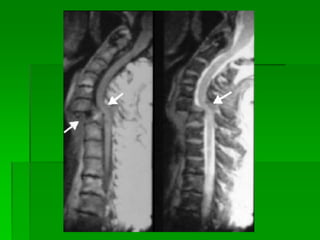

Fratura cervical

Angulação aguda do pescoço por

flexão e extensão violenta.

 Acidente automobilístico e mergulho

FISIOPATOLOGIA

Dr. Mônica KonckeFiuza Parolin TRAUMA FECHADO Fratura cervical Angulação aguda do pescoço por flexão e extensão violenta.  Acidente automobilístico e mergulho FISIOPATOLOGIA